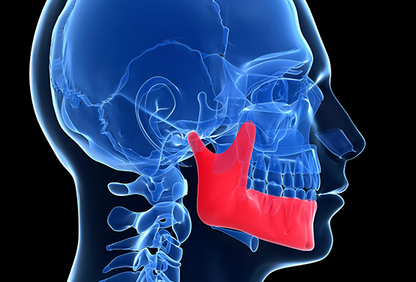

Jaw pain is usually caused by a temporomandibular disorder (TMD), a condition affecting the movement of the jaw. However, there are several other common causes of jaw pain. Below are some of the possible temporomandibular disorders and other conditions that can cause jaw pain.

TMJ disorders affect the bones, muscles, and ligaments surrounding the jaw joint. They can also affect the nerves associated with chronic facial pain. You may feel tenderness in your jaw that feels like a toothache, headache, or earache.

The pain from TMJ disorders can be worse while eating. They may also cause limited jaw movement. In some cases, TMJ disorders can cause a stiff neck and shoulder pain that spreads down the arm.